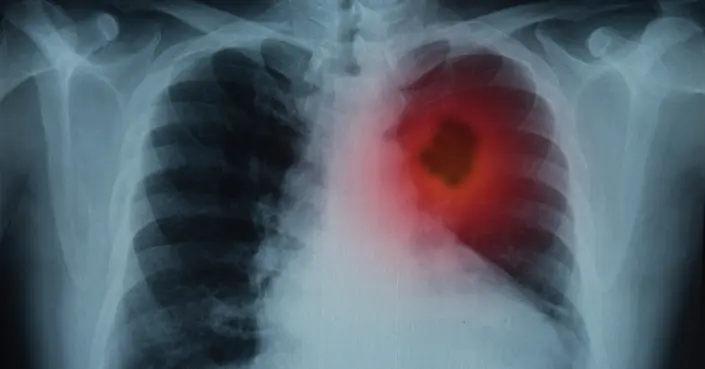

يُعد سرطان الرئة من الأمراض الخطيرة التي تؤثر على الآلاف حول العالم. فهم الأنواع المختلفة لهذا السرطان أمر حيوي للتشخيص السليم واختيار العلاج الأنسب. هل تعلم أن سرطان الرئة ليس نوعًا واحدًا، بل مجموعة من الأمراض التي تختلف في طريقة نشأتها وتطورها؟

سرطان الرئة هو نمو غير طبيعي وغير منضبط للخلايا داخل أنسجة الرئة. ينشأ هذا المرض عادةً في الخلايا المبطنة للشعب الهوائية (Bronchi) أو القصيبات الهوائية (Bronchioles) أو الحويصلات الهوائية. عندما تبدأ هذه الخلايا في الانقسام دون توقف، فإنها تشكل أورامًا يمكن أن تتدخل في وظيفة الرئة الطبيعية وتنتشر إلى أجزاء أخرى من الجسم.

يصنف الأطباء سرطان الرئة بشكل أساسي إلى فئتين رئيسيتين بناءً على مظهر الخلايا السرطانية تحت المجهر. هذا التصنيف المجهري ليس مجرد تفصيل علمي، بل هو أساس فهم السلوك البيولوجي للورم وكيفية استجابته للعلاجات المختلفة.